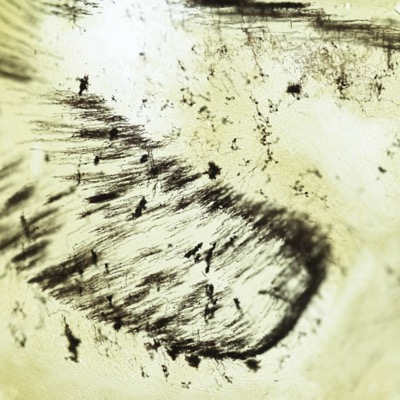

Cerebro